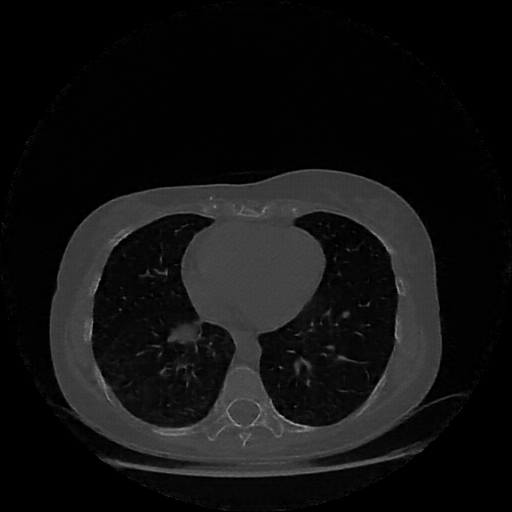

Image Grid

4Γ—3 grid: Rows show different image types (Original NATIVE, Reconstructed NATIVE, Original VENOUS, Generated VENOUS), Columns show windowing techniques (No Window, Lung Window, Mediastinum Window)

Original NATIVE CT scan (input)

Full window (WL 1023.5, WW 4095 β†’ Low βˆ’1024, High +3071)

Lung window (WL -600, WW 1500 β†’ Low βˆ’1350, High +150)

Mediastinum window (WL 40, WW 400 β†’ Low βˆ’160, High +240)